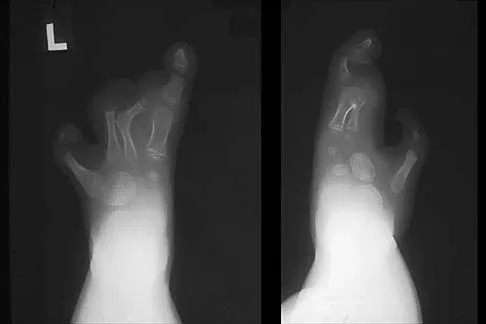

An 83-year-old woman with diabetes mellitus has a history of recurrent infection over the medial aspect of her great toe and has had a painless bunion for the past 45 years. Shoe wear modifications have failed to provide relief. Pedal pulses are palpable. Figures 30a and 30b show the clinical photograph and radiograph. Management should now consist of

Correct Answer: simple bunionectomy (medial exostectomy and capsular repair).

Explanation:

The presence of recurrent breakdown over the medial eminence despite shoe wear modifications is an indication for surgery. A number of factors must be considered when deciding on an appropriate course of treatment. These include age, activity level, joint congruency, joint degeneration, and the patient's symptoms and expectations. The indications for a simple bunionectomy are rather limited. In this patient, the goal of surgery is to alleviate the recurrent infection by removal of a large medial eminence. Because the bunion is painless and long-standing, it does not warrant treatment. Mizel MS, Miller RA, Scioli MW (eds): Orthopaedic Knowledge Update: Foot and Ankle 2. Rosemont, IL, American Academy of Orthopaedic Surgeons, 1998, pp 123-134.